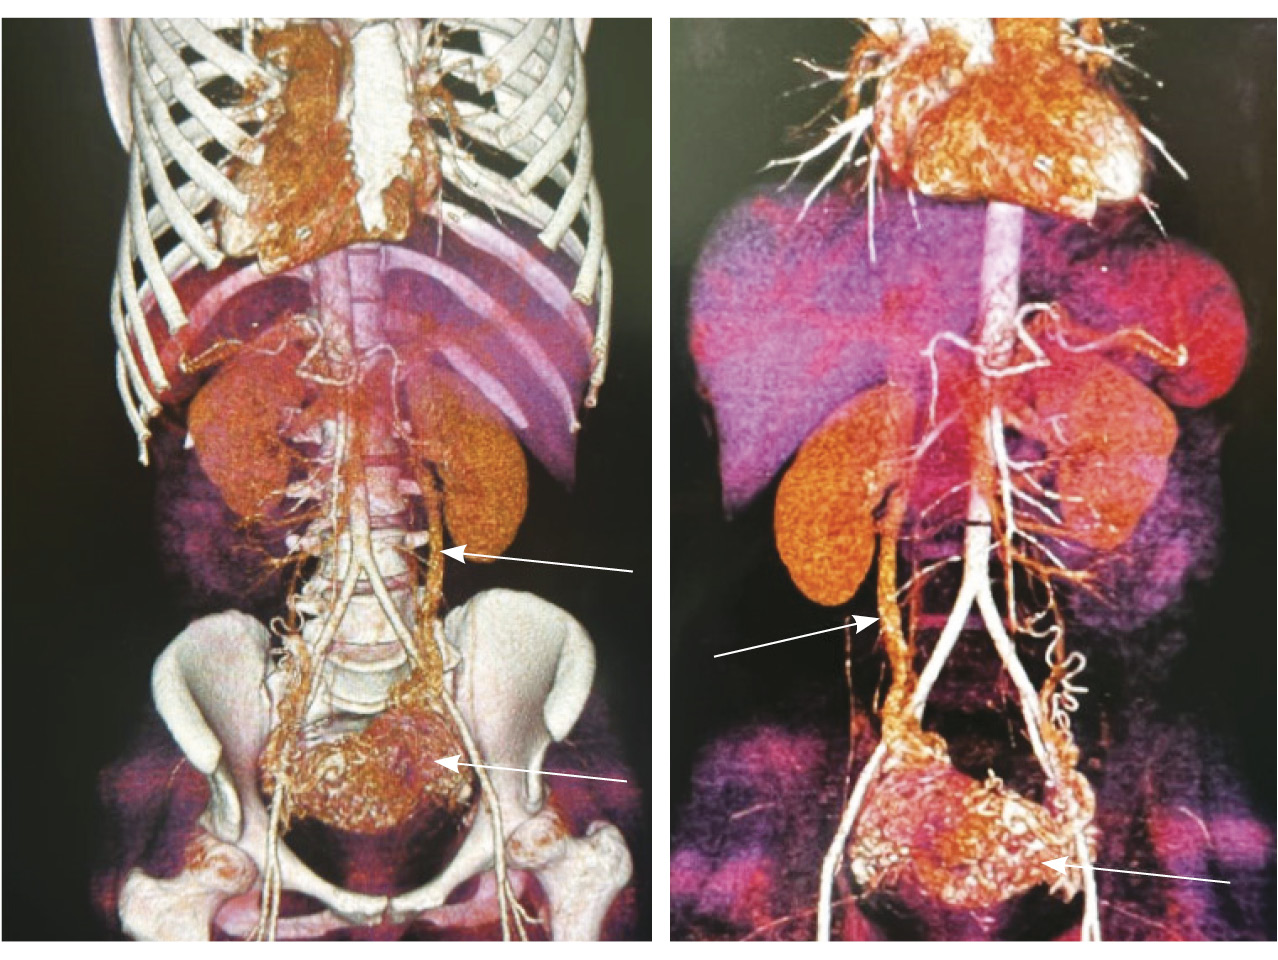

По наружной поверхности нижнего маточного сегмента и в параметрии определяется наличие полнокровной сосудистой сети с артериовенозными анастомозами. При контрастировании визуализируются фрагментарные участки гиперваскулярного накопления контраста вышеописанным образованием в рубцовой нише, а также определяется наличие артериовенозной сосудистой мальформации (рис. 2).

Рис. 2. Магнитно-резонансная томограмма, динамическое контрастное усиление в режиме Т1-взвешенного изображения FS. До контраста (А), в раннюю артериальную фазу (Б), паренхиматозную фазу (В), выделительную фазу (Г) определяются многочисленные патологические сосуды, зоны неоангиогенеза, сосудистые шунты как в стенке матки, так и в параметрии по типу артериовенозной мальформации

Для детализации сосудистого компонента артериовенозной мальформации, в том числе с целью планирования дальнейшей лечебной тактики, пациентке выполнено КТ-исследование (рис. 3). Обнаружено: тело матки увеличено, определяется образование в полости матки неясного генеза. В стенках матки сосудистая артериальная сеть с ранним сбросом контрастного вещества во внутреннюю подвздошную вену с двух сторон (диаметром 0,7 см справа, 0,8 см – слева), правую яичниковую вену (диаметром до 1,2 см), левую яичниковую вену (диаметром до 0,6 см).

Рис. 3. Компьютерная томограмма органов таза с контрастированием. Тело матки увеличено, в стенках матки сосудистая артериальная сеть (стрелки) с ранним сбросом контрастного вещества во внутреннюю подвздошную вену с двух сторон, правую и левую яичниковые вены (стрелка)